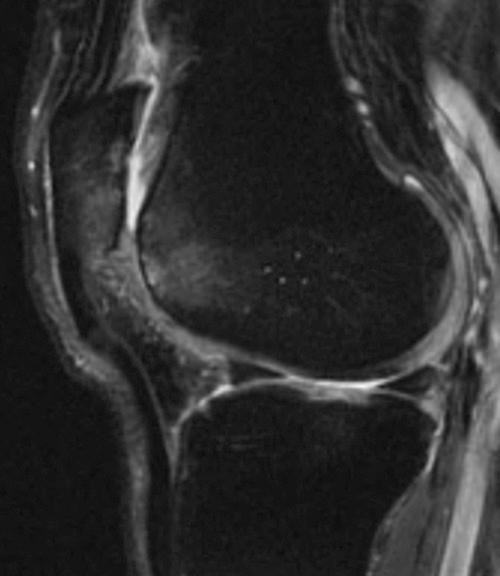

Physical examination and imaging evaluation including standard radiographs are crucial in identifying evidence of malalignment or instability. Magnetic resonance imaging provides valuable information about concomitant soft tissue injuries to the medial stabilizers as well as injuries to the articular cartilage, including chondral shears and osteochondral fractures. Quantitative magnetic resonance imaging assessing the ultrastructure of cartilage has shown high correlation with histology and may be useful for timing surgery.

Evaluation of patellofemoral disorders is complex and requires a comprehensive assessment. Recent advancements in imaging have made possible a more precise evaluation of the individual anatomy of the patient, addressing issues of malalignment, instability, and underlying cartilage damage.